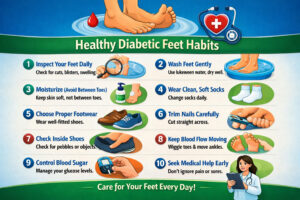

10 Daily Habits That Could Save Your Feet If you’re living with diabetes, your feet deserve special attention every single...

10 Daily Habits That Could Save Your Feet If you’re living with diabetes, your feet deserve special attention every single...